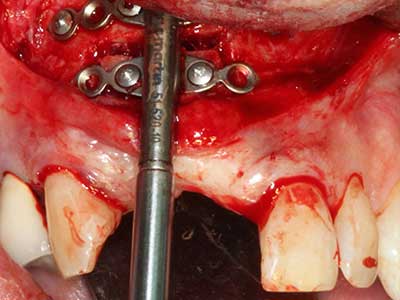

Piezo surgery has additional advantages when harvesting bone blocks. In addition to the high precision with osteotomy described above, the use of the thin saw tips specifically minimizes loss of material. Greater loss of material during harvesting can be expected with the thicker instrument tips, particularly when using Lindemann drills (Lakshmiganthan, Gokulanathan et al. 2012). The basal separation, which is necessary particularly for retromolar block transplants, is simplified by specially designed rectangular saws, with the result that piezo surgery is viewed as a precise, simple and safe procedure for harvesting retromolar bone blocks (Happe 2007) (Fig. 1-12).

Fig. 1: Preparation of a bone cover with the Piezomed (W&H Salzburg, Austria).

Fig. 3: Basal separation of the block is easier with specially angled attachments.